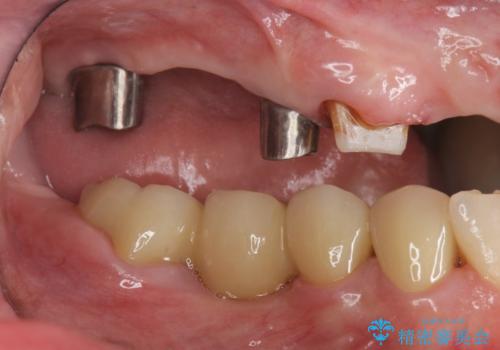

多発した虫歯による咬合崩壊 インプラントを用いた全顎治療

歯の破折・再発した大きな虫歯・根尖病変・歯の欠損、これらの問題を根管治療・歯周外科・インプラント治療・セラミック補綴を行うことで一つづつ解決し安定した咬合状となるよう治療を進めます。

インプラント治療の注意事項(リスク・副作用など)

- 糖尿病、肝硬変、心臓病等の場合、インプラント治療ができない可能性があります

- 高血圧、貧血・不整脈等の場合、インプラント治療後に治癒不全を招く可能性があります